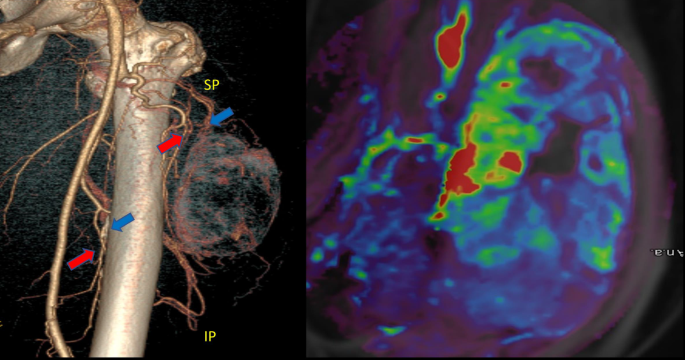

A combination of morphologic, qualitative, and semiquantitative PWI/DCE features has helped differentiate responders from partial/non-responders (Figs. 5, 6 and 7). Our results have shown that a “Capsular” pattern is a typical PWI/DCE morphologic feature in the responder group (P = 1.49 × 10−7). A clinical radiologist can readily recognize this pattern without the need for post-processing software as is required for first- and high-order radiomic feature extraction. However, suboptimal responders tend to display a “Unipolar” or “Bipolar” pattern at PRT. The finding of the described patterns appears to follow a set pattern where “capsular” is the latest pattern of response, following “unipolar” and “bipolar,” respectively. This progression may be partly linked to the presence of an underlying “sarcoma organ model” with a dominant vascular supply at the superior pole, a secondary vascular supply at the inferior pole, and a likely arterial perfusion gradient from superior to inferior and from peripheral to central/equatorial, as illustrated in Fig. 12.

Sarcoma organ model of undifferentiated pleomorphic sarcoma. On the left, a 3D CT-angiogram (CTA) reconstruction demonstrates a superior pole vascular supply dominance. A secondary, inferior vascular pole is also seen. On the right, a post-radiation PWI/DCE wash-in map in a UPS with < 90% TIN demonstrates arterial perfusion gradient from hypervascular residual solid components in proximity to arterial supply (superior pole/unipolar enhancement) to a central/equatorial necrosis in correlation with hypoxic tumor. The figure was modified with permission from the authors of RF Valenzuela et al.30.